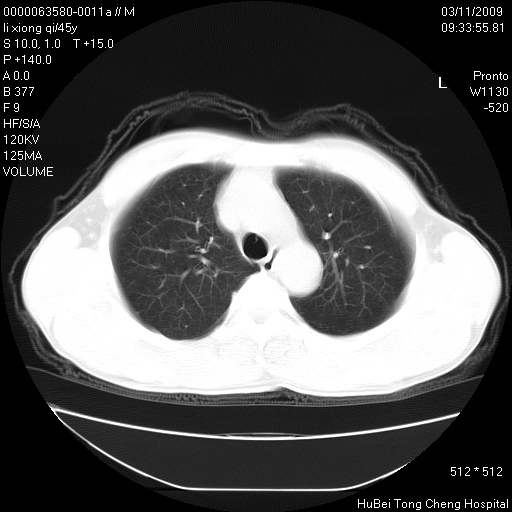

患者 男,45岁。胸痛,咳嗽伴痰中带血1月余。

临床诊断:肺结核?

胸部ct轴位平扫(层厚10mm,螺距1.5,重建间隔10mm),图像如下: